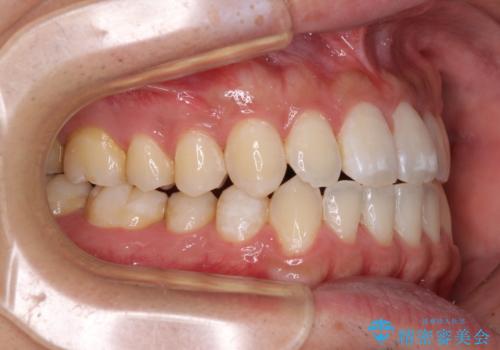

下顎前歯と上顎の部分矯正

- 上下の前歯の叢生を気にして来院された患者様です。

前歯のみの矯正治療を希望でしたが、上顎臼歯が舌側転位していたため、上顎は全体を、下顎は前歯のみを矯正治療することとしました。

矯正治療は上下全顎を行うことが大前提ですが、費用などの点から、今回は部分矯正を選択することとなりました。

患者様本人は咬みにくさを感じていないようですが、部分矯正は咬み合わせの改善が困難であることが多く、咬みにくさが残ることがあります。